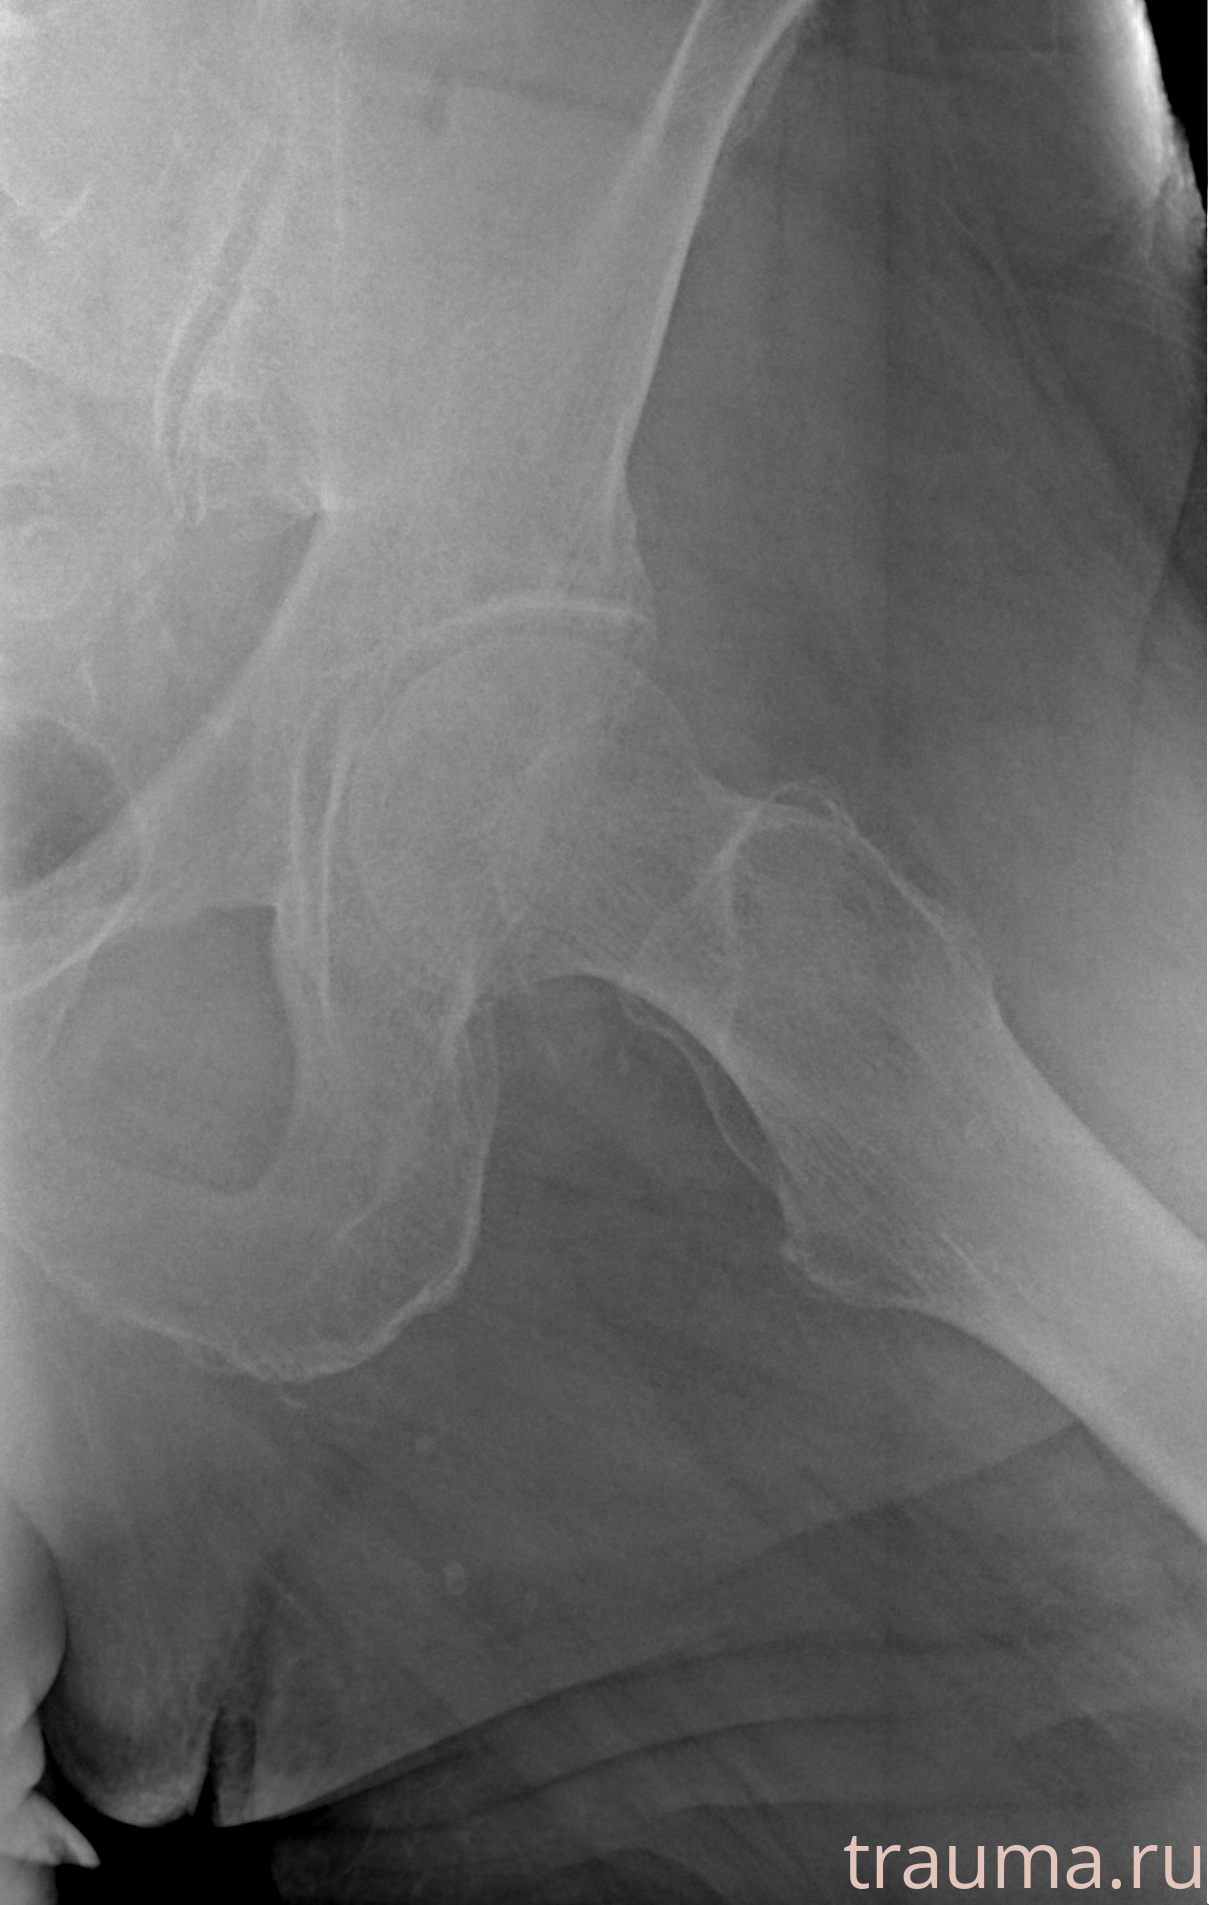

Рентгенограммы

Рентген на дому: по вашему адресу приезжает врач-рентгенолог, травматолог-ортопед с мобильным рентгеновским аппаратом, проводит диагностику травмы или заболевания, делает необходимые рентгенограммы, дает рекомендации по дальнейшему лечению. Получить качественные снимки в домашних условиях возможно благодаря уникальной методике, разработанной МосРентген Центром для института  Склифосовского